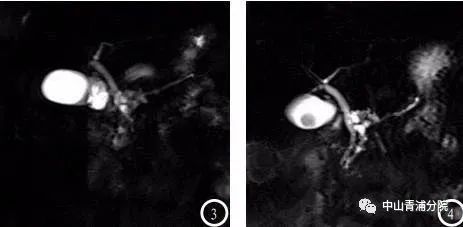

(胆囊结石MRI及MRCP表现)

患者往往有胆绞痛发作的病史,发作部位多位于上腹部或右上腹部,一般持续15分钟以上,疼痛可放射至右肩或后背,常伴有恶心或呕吐。大多数胆囊结石可以通过腹部B超、CT、内镜超声或磁共振胰胆管成像(MRCP)等明确诊断。